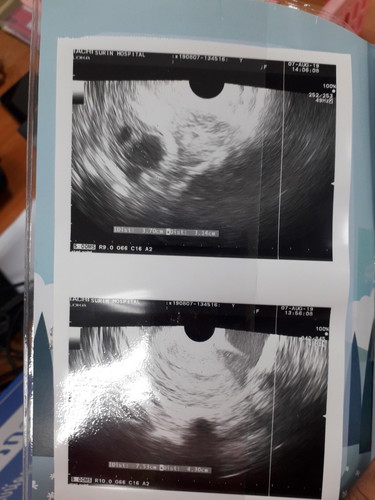

ตอนนี้ท้องได้5วีคแต่ไปซาวด์มาไม่เจอน้องประมานกี่วีคคะ? จะเห็น กลัวท้องลมมากค่ะ

5 วีค ยังเล๊กกกกก มากจ้า น้อยคนที่จะเห็น ยิ่งถ้าซาวด์ทางหน้าท้อง ถ้าตัวอ่อนยังเล็กมากๆ หรือเป็นคนหน้าท้องหนา ยิ่งไม่เห็นค่ะแม่ ทางช่องคลอดจะพอมีลุ้นมากกว่าค่ะ ทั้งนี้เป็นไปได้ว่า อายุครรภ์อาจจะน้อยกว่าที่นับ เพราะไข่อาจจะตกช้ากว่ากำหนด ตัวอ่อนยังเล็กมากอยู่ จึงยังไม่พบ ก็เป็นได้ค่ะแม่ แต่ 5 วีคยังเล็กมากๆจริงๆจ้า ยังไม่เห็นไม่แปลกจ้า ทานโฟลิคทุกวัน พักผ่อนเยอะๆ นะคะ ซาวด์ครั้งหน้าอาจจะได้เจอกันแล้วจ้า

ซาวผ่านช่องคลอดหรือป่าวค่ะ ของเราซาวเมื่อเช้าเห็นหัวใจกระพริบๆๆ 5วีค5วันนี้ ถ้าซาวหน้าท้องจะยังไม่เตอนะค่ะ

8 week ซาวด์ทางช่องคลอดค่ะ ได้ยินเสียงหัวใจน้องด้วยค่ะ ใจเย็นๆนะค่ะ ช่วงนี้รักษาสุขภาพมากๆค่ะ 😍

ตอนนี้เราก็ เครียดค่ะ ท้องได้7วีก 2วัน ซาวไม่เจอตัวน้องเลยเจอแต่ถุงตั้งครรภ์